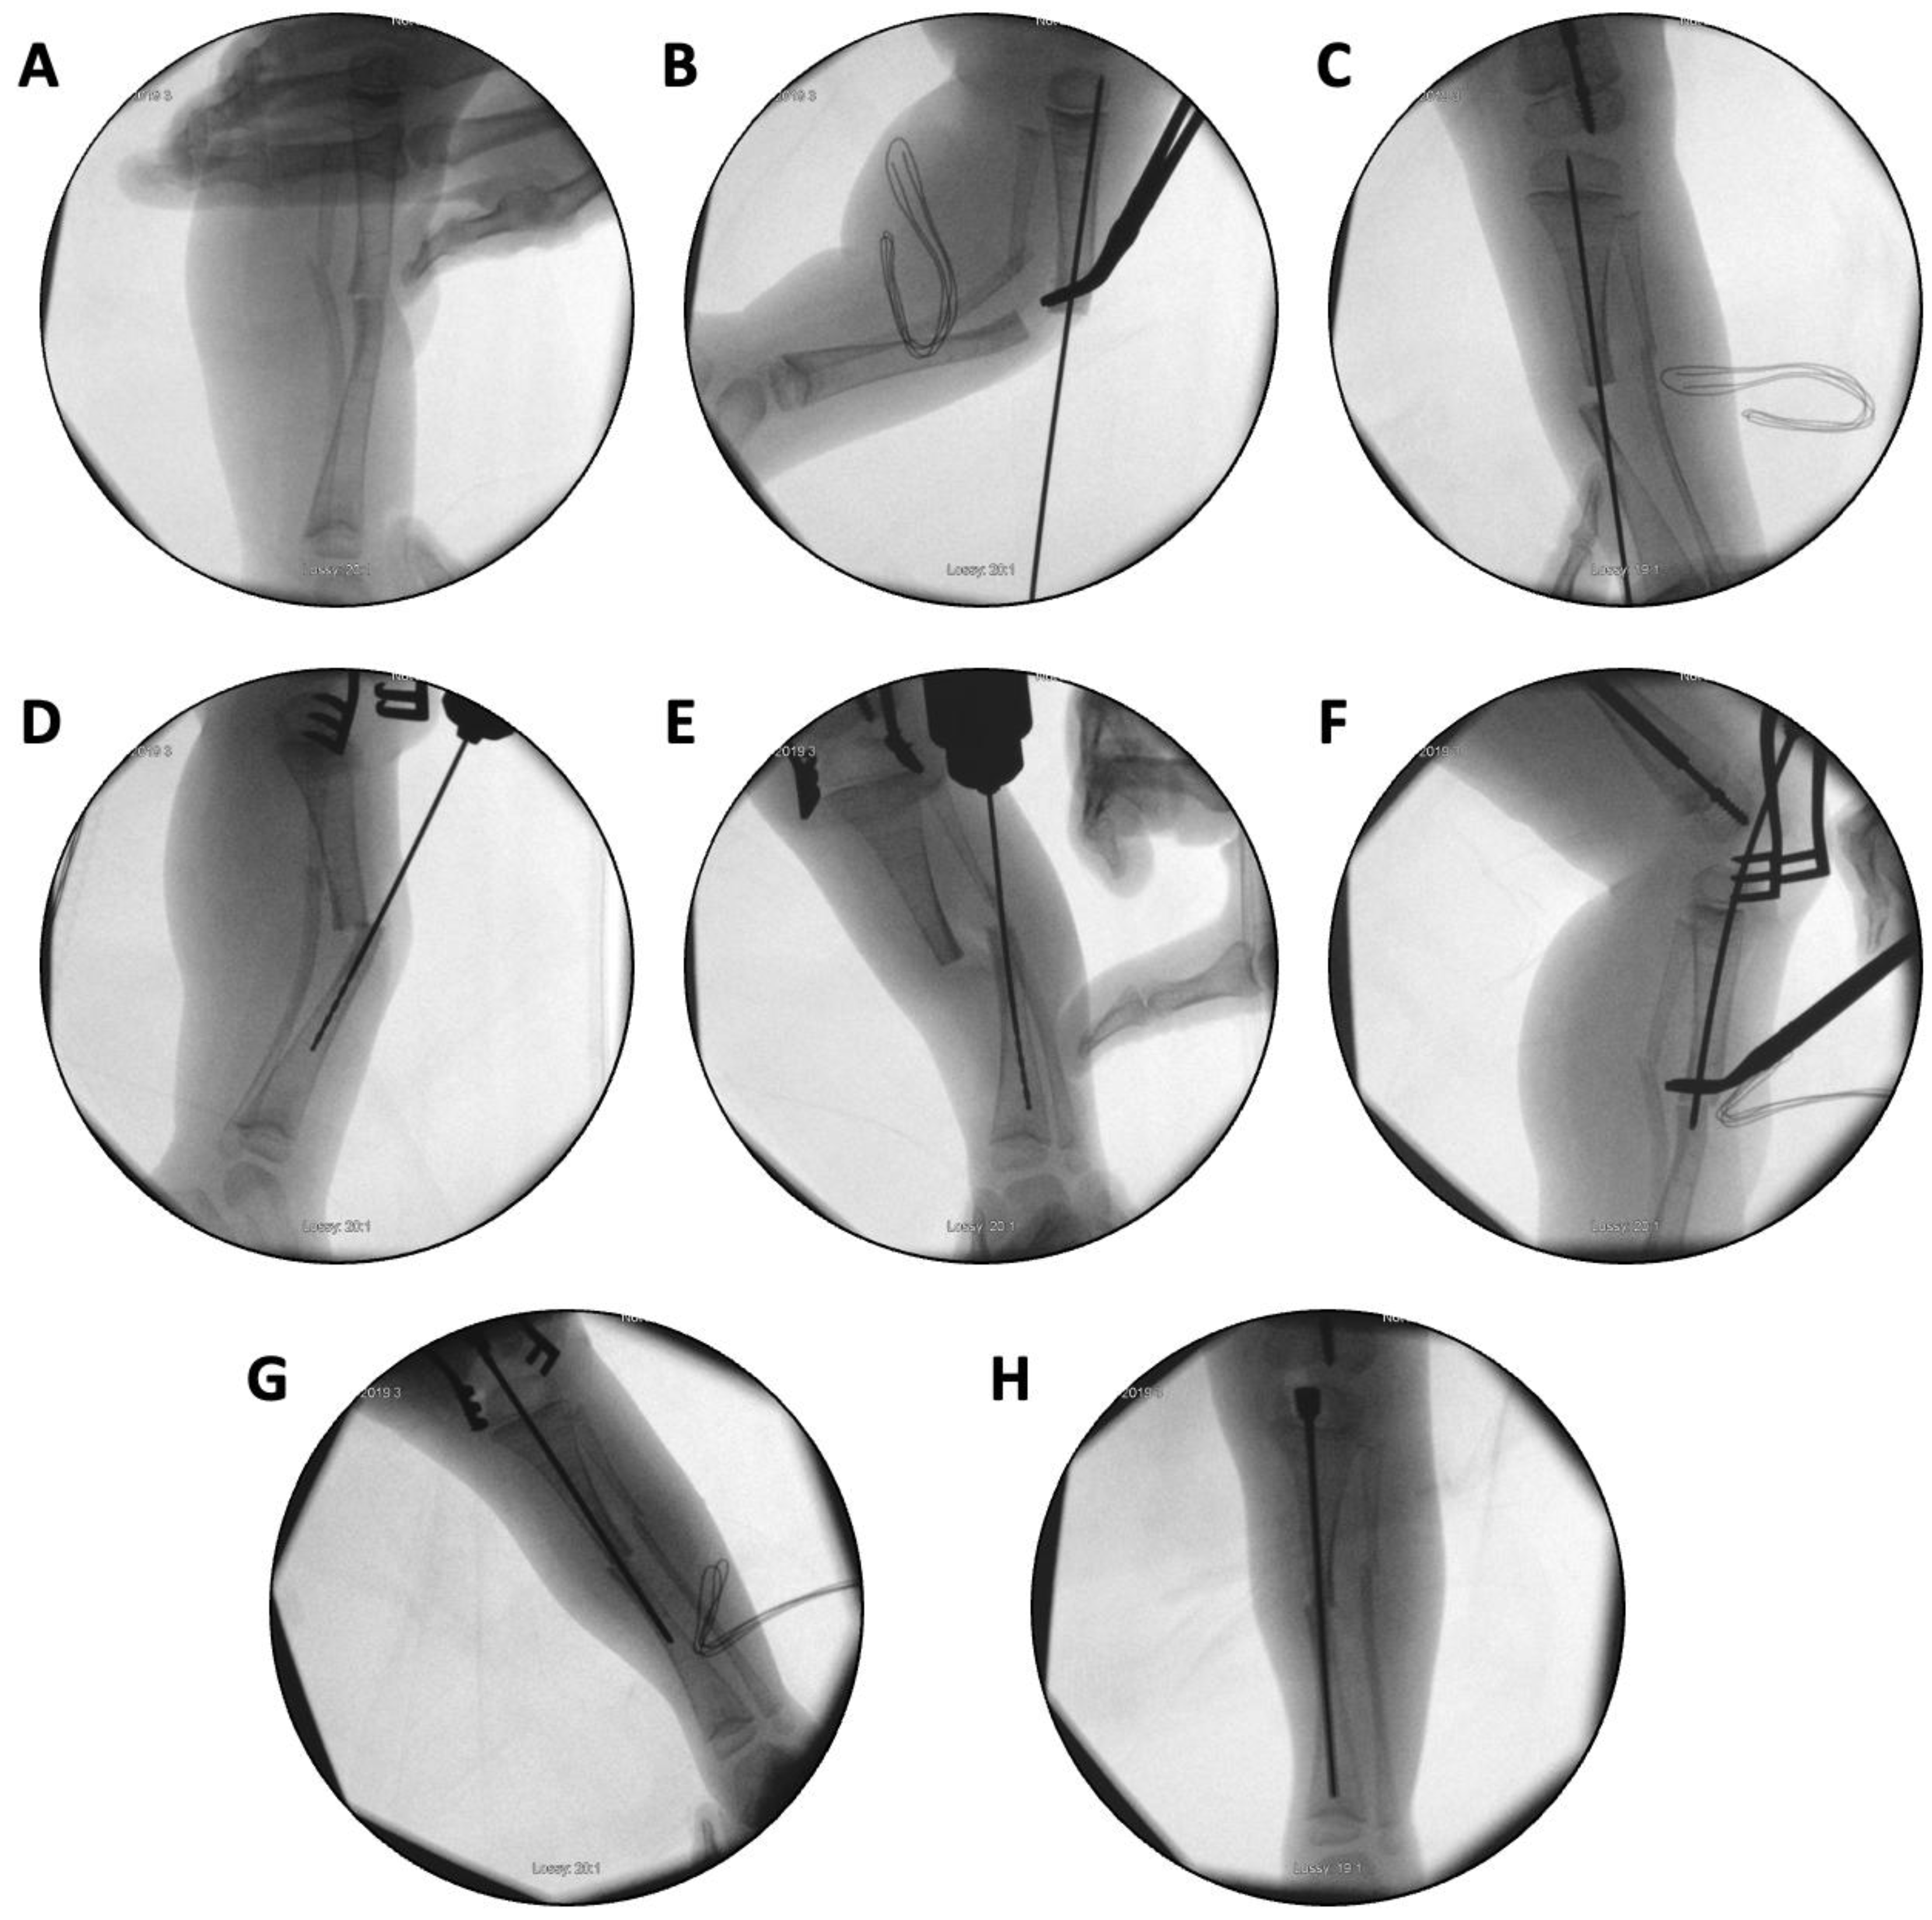

In the first case, a three-year-old skeletally immature girl diagnosed with OI type III presented for surgical correction of significant right tibial bowing using a SLIM nail. After identifying the CORA (Figure 8), an anterior opening-wedge osteotomy was performed at the midshaft of the right tibia to realign the bone (Figure 9A). The proximal canal was sequentially reamed from the osteotomy site to accommodate the SLIM nail, and a medial parapatellar approach was used to retrieve the reamer at the level of the knee (Figure 9B-C). The distal tibia was similarly reamed up to the distal physis (Figure 9D-E). The SLIM nail was inserted through the knee and positioned centrally within the canal with good bony contact on all sides, with the proximal threading positioned in the epiphysis (Figure 9F-H). Fluoroscopy confirmed excellent alignment, and no additional internal fixation was needed. In this case, the indication for using a SLIM nail was the narrow intramedullary canal of the tibia in a skeletally immature patient requiring deformity correction. A larger nail could not be used due to anatomical limitations, making the SLIM nail the appropriate choice.

Figure 9. (A-H): Series of intraoperative fluoroscopy images demonstrating insertion of the SLIM nail. A – After osteotomy, the fracture is reduced. B – Lateral view of proximal reaming through the osteotomy site. C – AP view of proximal reaming through the osteotomy site. D – Lateral view of distal reaming through the osteotomy site. E – AP view distal reaming through the osteotomy site. F – Insertion of the SLIM nail. G – SLIM nail is gradually advanced past the osteotomy site. H – AP view of installed SLIM nail, with proximal threading in the epiphysis.